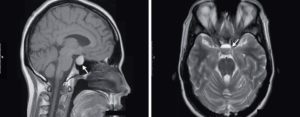

Если сканировать гипофиз со стороны лица (фронтальная плоскость), то орган похож на прямоугольник. Его нижняя сторона соответствует дну турецкого седла, а верхняя бывает выпуклой, вогнутой или прямой.

От передней стенки гипофиза до задней и от правой до левой размер не меняется, поэтому об увеличении органа судят по его вертикальному размеру.

В норме он не больше 4-7 см, у подростков, в конце беременности и в раннем послеродовом периоде его возрастание до 12 см является вариантом нормы.

К отклонениям также не относится легкая асимметрия контура, незначительное смещение воронки, которая соединяет гипофиз и гипоталамус при отсутствии других изменений ткани.

Ткань передней доли однородная и имеет такую же плотность, как и белое вещество мозга. Непосредственно у ножки могут быть светлые пузырьки, которые являются скоплением коллоидного вещества.

- Пустое турецкое седло. По внутренней поверхности турецкого седла «распластан» гипофиз. Его покрытие (диафрагма) при этом провисает в полость. Гипофизарная ткань становится похожа на тонкий полумесяц толщиной 2 мм.